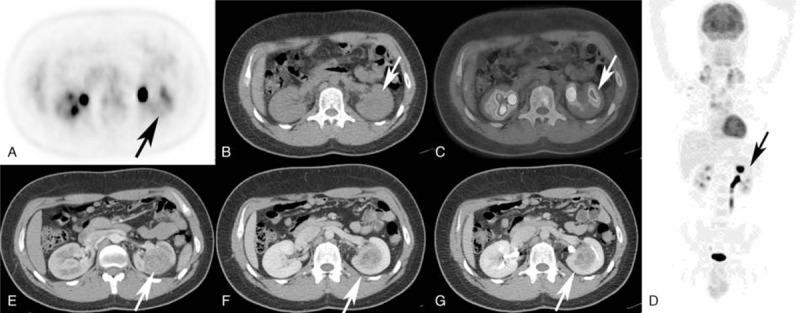

The objective of this study was to compare the diagnostic accuracy of positron emission tomography/low-dose computed tomography (PET/ldCT) versus the same technique implemented by contrast-enhanced computed tomography (ceCT) in staging Hodgkin's disease (HD).Forty patients (18 men and 22 women, mean age 30 ± 9.6) with biopsy-proven HD underwent a PET/ldCT study for initial staging including an unenhanced low-dose computed tomography for attenuation correction with positron emission tomography acquisition and a ceCT, performed at the end of the PET/ldCT scan, in the same exam session. A detailed datasheet was generated for illness locations for separate imaging modality comparison and then merged in order to compare the separate imaging method results (PET/ldCT and ceCT) versus merged results positron emission tomography/contrast-enhanced computed tomography (PET/ceCT). The nodal and extranodal lesions detected by each technique were then compared with follow-up data that served as the reference standard.No significant differences were found at staging between PET/ldCT and PET/ceCT in our series. One hundred and eighty four stations of nodal involvement have been found with no differences in both modalities. Extranodal involvement was identified in 26 sites by PET/ldCT and in 28 by PET/ceCT. We did not find significant differences concerning the stage (Ann Arbor).Our study shows a good concordance and conjunction between PET/ldCT and ceCT in both nodal and extranodal sites in the initial staging of HD, suggesting that PET/ldCT could suffice in most of these patients.

本研究的目的是比较正电子发射断层扫描/低剂量计算机断层扫描(PET/ldCT)与通过对比增强计算机断层扫描(ceCT)实施的相同技术在霍奇金淋巴瘤(HD)分期中的诊断准确性。40例经活检证实为HD的患者(18例男性和22例女性,平均年龄30±9.6岁)接受了PET/ldCT初始分期检查,包括用于正电子发射断层扫描采集衰减校正的非增强低剂量计算机断层扫描,以及在PET/ldCT扫描结束时于同一检查环节进行的ceCT。为进行单独成像模态比较生成了详细的疾病位置数据表,然后合并以比较单独成像方法结果(PET/ldCT和ceCT)与合并结果正电子发射断层扫描/对比增强计算机断层扫描(PET/ceCT)。然后将每种技术检测到的淋巴结和结外病变与作为参考标准的随访数据进行比较。在我们的系列研究中,PET/ldCT和PET/ceCT在分期方面未发现显著差异。共发现184个淋巴结受累部位,两种模态均无差异。PET/ldCT在26个部位发现结外受累,PET/ceCT在28个部位发现结外受累。我们未发现关于分期(Ann Arbor分期)的显著差异。我们的研究表明,在HD初始分期中,PET/ldCT与ceCT在淋巴结和结外部位均具有良好的一致性和关联性,这表明在大多数此类患者中PET/ldCT可能就足够了。